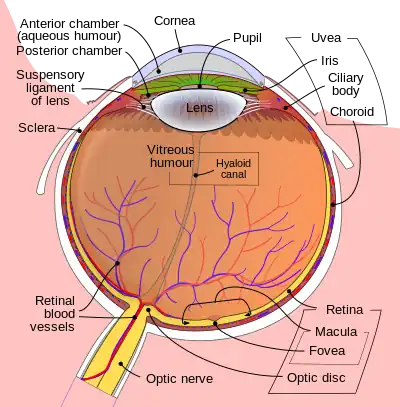

Schematic diagram of the human eye. | |

Position in the eye

The lens is located towards the front part of the vertebrate eye called the anterior segment which includes the cornea and iris positioned in front of the lens. The lens is held in place by the suspensory ligaments (Zonule of Zinn),[1] attaching the lens at its equator to the rest of the eye[2][3] through the ciliary body. Behind the lens is the jelly-like vitreous body which helps hold the lens in place. At the front of the lens is the liquid aqueous humor which bathes the lens with nutrients and other things. Land vertebrate lenses usually have an ellipsoid, biconvex shape. The front surface is less curved than the back. A human adult the lens is typically about 10mm in diameter and 4mm thick though changes shape with accommodation and size due to grow throughout a person's lifetime.[4]

The lens has three main parts: the lens capsule, the lens epithelium, and the lens fibers. The lens capsule is a relatively thick basement membrane forming the outermost layer of the lens. Inside the capsule much thinner lens fibers form the bulk of the lens. The cells of the lens epithelium form a thin layer between the lens capsule and the outermost layer of lens fibers at the front of the lens but not the back. The lens itself lacks nerves, blood vessels, or connective tissue.[5] Anatomists will often refer to positions of structures in the lens by describing it like a globe of the world. The front and back of the lens are referred to as the anterior and posterior "poles", like the North and South poles. The "equator" is the outer edge of the lens often hidden by the iris and is the area of most cell differentiation. As the equator is not generally in the light path of the eye the structures involved with metabolic activity avoid scattering light that would otherwise affect vision.